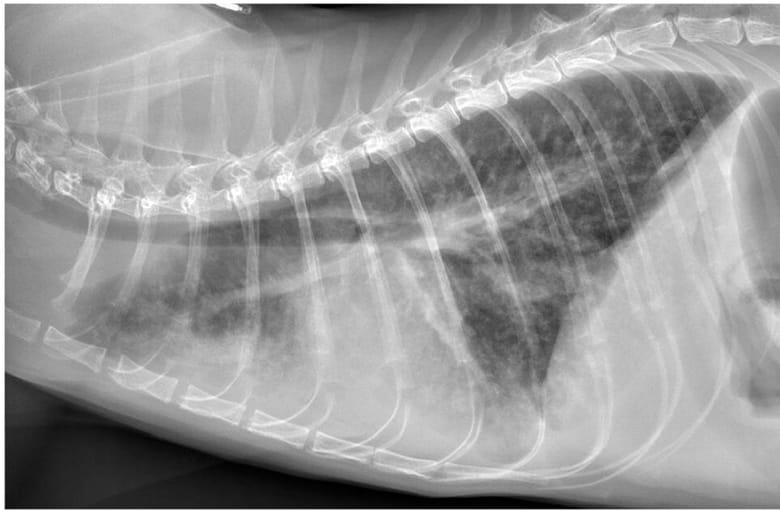

Right lateral thoracic radiograph (confirmed case, cat 15). Findings for this case included a severe diffuse interstitial pattern with numerous small nodules throughout all lung lobes, mild diffuse bronchial pattern, mild ventral alveolar pattern and mild pleural effusion. Pleural effusion silhouettes with the cranial and ventral margins of the cardiac silhouette, resulting in border effacement in those regions

The study included 35 cats (18 with definitive FIP and 17 with presumptive FIP). Thoracic radiographs were abnormal in 91.4% (32/35) of cases. Pleural effusion was present in 37.1% (13/35), mostly bilateral. Pulmonary abnormalities were seen in 71.4% (25/35) of cats, with the most common pattern being unstructured interstitial (84%), followed by bronchial (44%), alveolar (40%), and nodular (12%). Sternal lymphadenopathy was present in 45.7% (16/35). Cardiomegaly was observed in 17.1% (6/35) and was linked to myocarditis, pericardial effusion, or high-output cardiac states. Pulmonary histopathology, available for 17 cats, showed pulmonary edema (94%), fibrinosuppurative pleuritis (76%), and histiocytic vasculitis (59%).